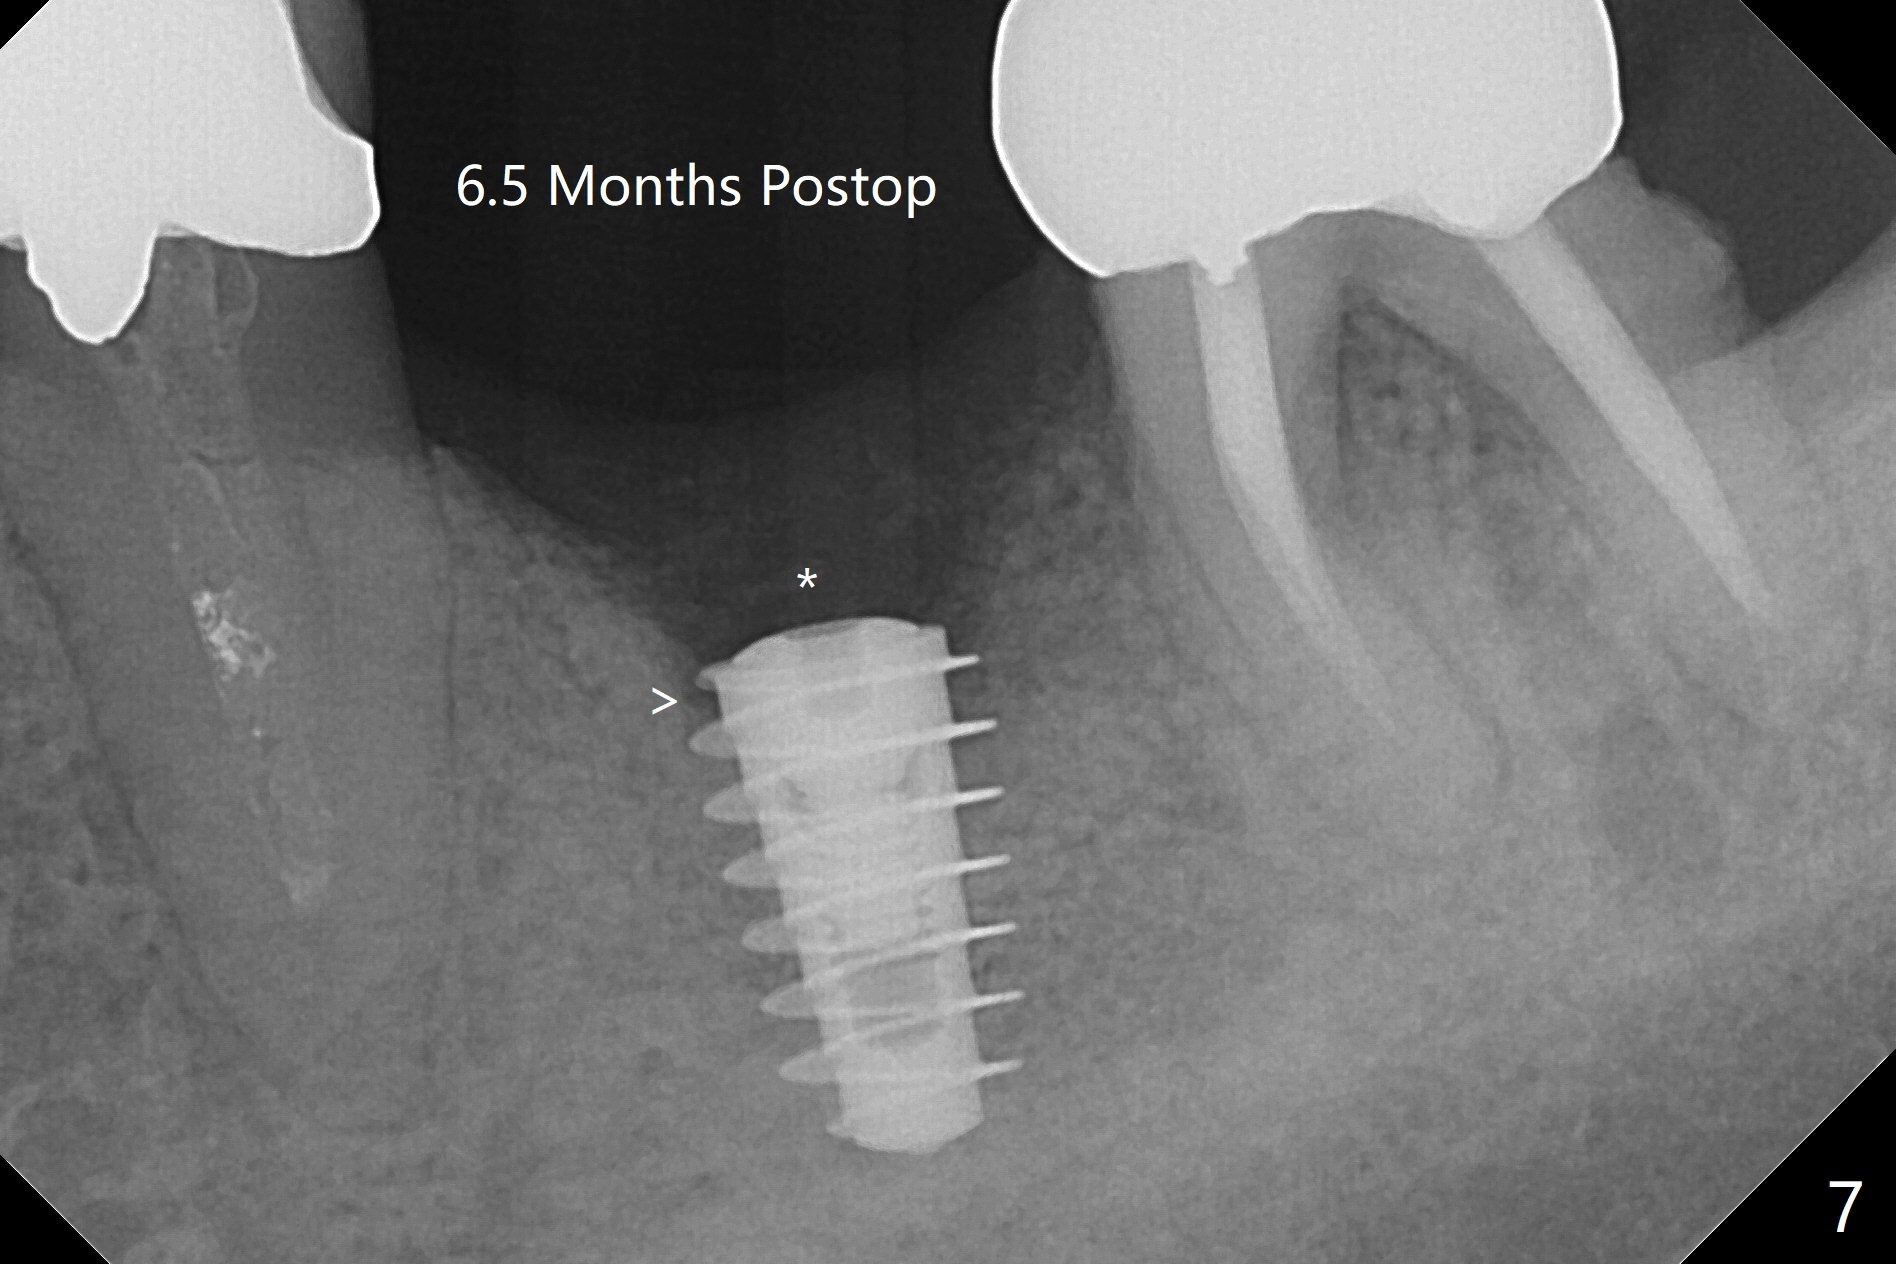

When the patient returns 4 months post implant removal and bone graft, the ridge at #19 is concave with a small hole which communicates with the underlying bone (Fig.1 <). The low density bone in the middle of the socket is ignored (Fig.2 *, 3 S (soft)). With under drilling, primary stability of tissue-level taps is lower. A bone-level dummy implant is placed with low torque (Fig.4). After removal of granulation tissue distal to the osteotomy, a larger implant is inserted with ~15 Ncm; mixture of autogenous bone and allograft is packed (Fig.5 *). The latter is covered by 12x12 mm BioXclude and sutured with 4/0 Chromic Gut tension free. 植牙后6.5月牙槽嵴饱满,角化龈宽(图六(刚开始浸润麻醉))。术后6.5月切开证实植体上面没有骨质覆盖(如图七:*),第一螺纹可能暴露(>)。由于骨质吸收,大号基台置入没阻挡,或者困难(图八),第一螺纹暴露(>)需要再次植骨(图九:*)。放置大号基台(6x6(4)毫米)和植骨使萎缩牙槽嵴部分得到修复(图十,与Uncover前(图六)对比)。Uncover时即刻置入修复性基台好处是利用基台牙龈外部分强化牙周敷料固定,基台中央放置一个棉球后,敷料可以插入基台中央进一步增加固位(图十一(舌侧观):*)。